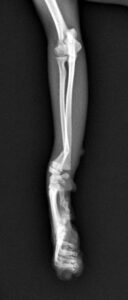

5~6歳以上の去勢手術をしていないオス犬に多い病気ですが、メス犬や去勢した犬に起こることもあります。お尻の筋肉が萎縮した結果、筋肉の隙間から直腸や膀胱が皮膚の下にとびでてしまいます。これにより便が出にくくなったり膀胱炎になったりします。手術をすることで機能回復および今後の致死的な状況を回避することができます。当院では去勢手術→結腸固定→前立腺固定→骨盤隔膜構成筋の縫縮→内閉鎖筋フラップ→浅臀筋フラップの順で通常腹側・臀部左右両側同時に行います。また老化以外に、筋肉が萎縮する原因があったり、腹圧がかかる原因があったりする場合も多いので、再発防止のためそれらの診断・治療も重要です。今回のワンちゃんも無事手術も終わり元気に退院しました。よかったね。